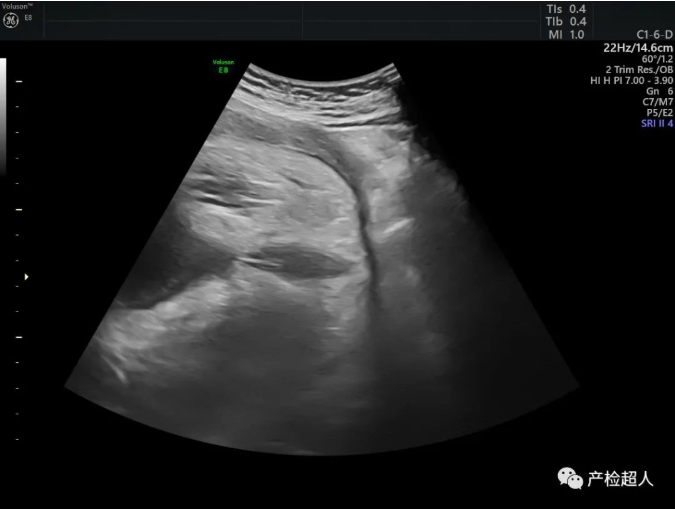

37周,腹腔及肛门附近图像如下,您作何考虑,欢迎留言,下期答案揭晓。